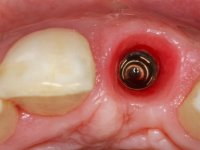

3) Colocação de um implante no espaço criado na zona do 21 associada a uma regeneração óssea guiada da zona,

Os cotos de óxido de zircónio são dos assuntos mais debatidos em implantologia. A sua resistência à fractura, as conexões externas e internas, a interacção entre o parafuso de retenção e o coto – todos estes assuntos são abordados repetidamente. No entanto, todos parecem concordar que os cotos de óxido de zircónio apresentam resultados altamente previsíveis, especialmente na restauração de dentes anteriores. Outro argumento em favor dos cotos de óxido de zircónio é a alta biocompatibilidade do material.